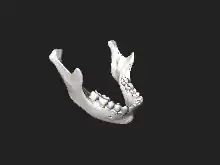

Mandible

In anatomy, the mandible, lower jaw or jawbone is the largest, strongest and lowest bone in the human facial skeleton.[2] It forms the lower jaw and holds the lower teeth in place. The mandible sits beneath the maxilla. It is the only movable bone of the skull (discounting the ossicles of the middle ear).[3] It is connected to the temporal bones by the temporomandibular joints.

The mandible consists of:

- The body, found at the front

- A ramus on the left and the right, the rami rise up from the body of the mandible and meet with the body at the angle of the mandible or the gonial angle.

Body

Ramus

The ramus (Latin: branch) of the human mandible has four sides, two surfaces, four borders, and two processes.